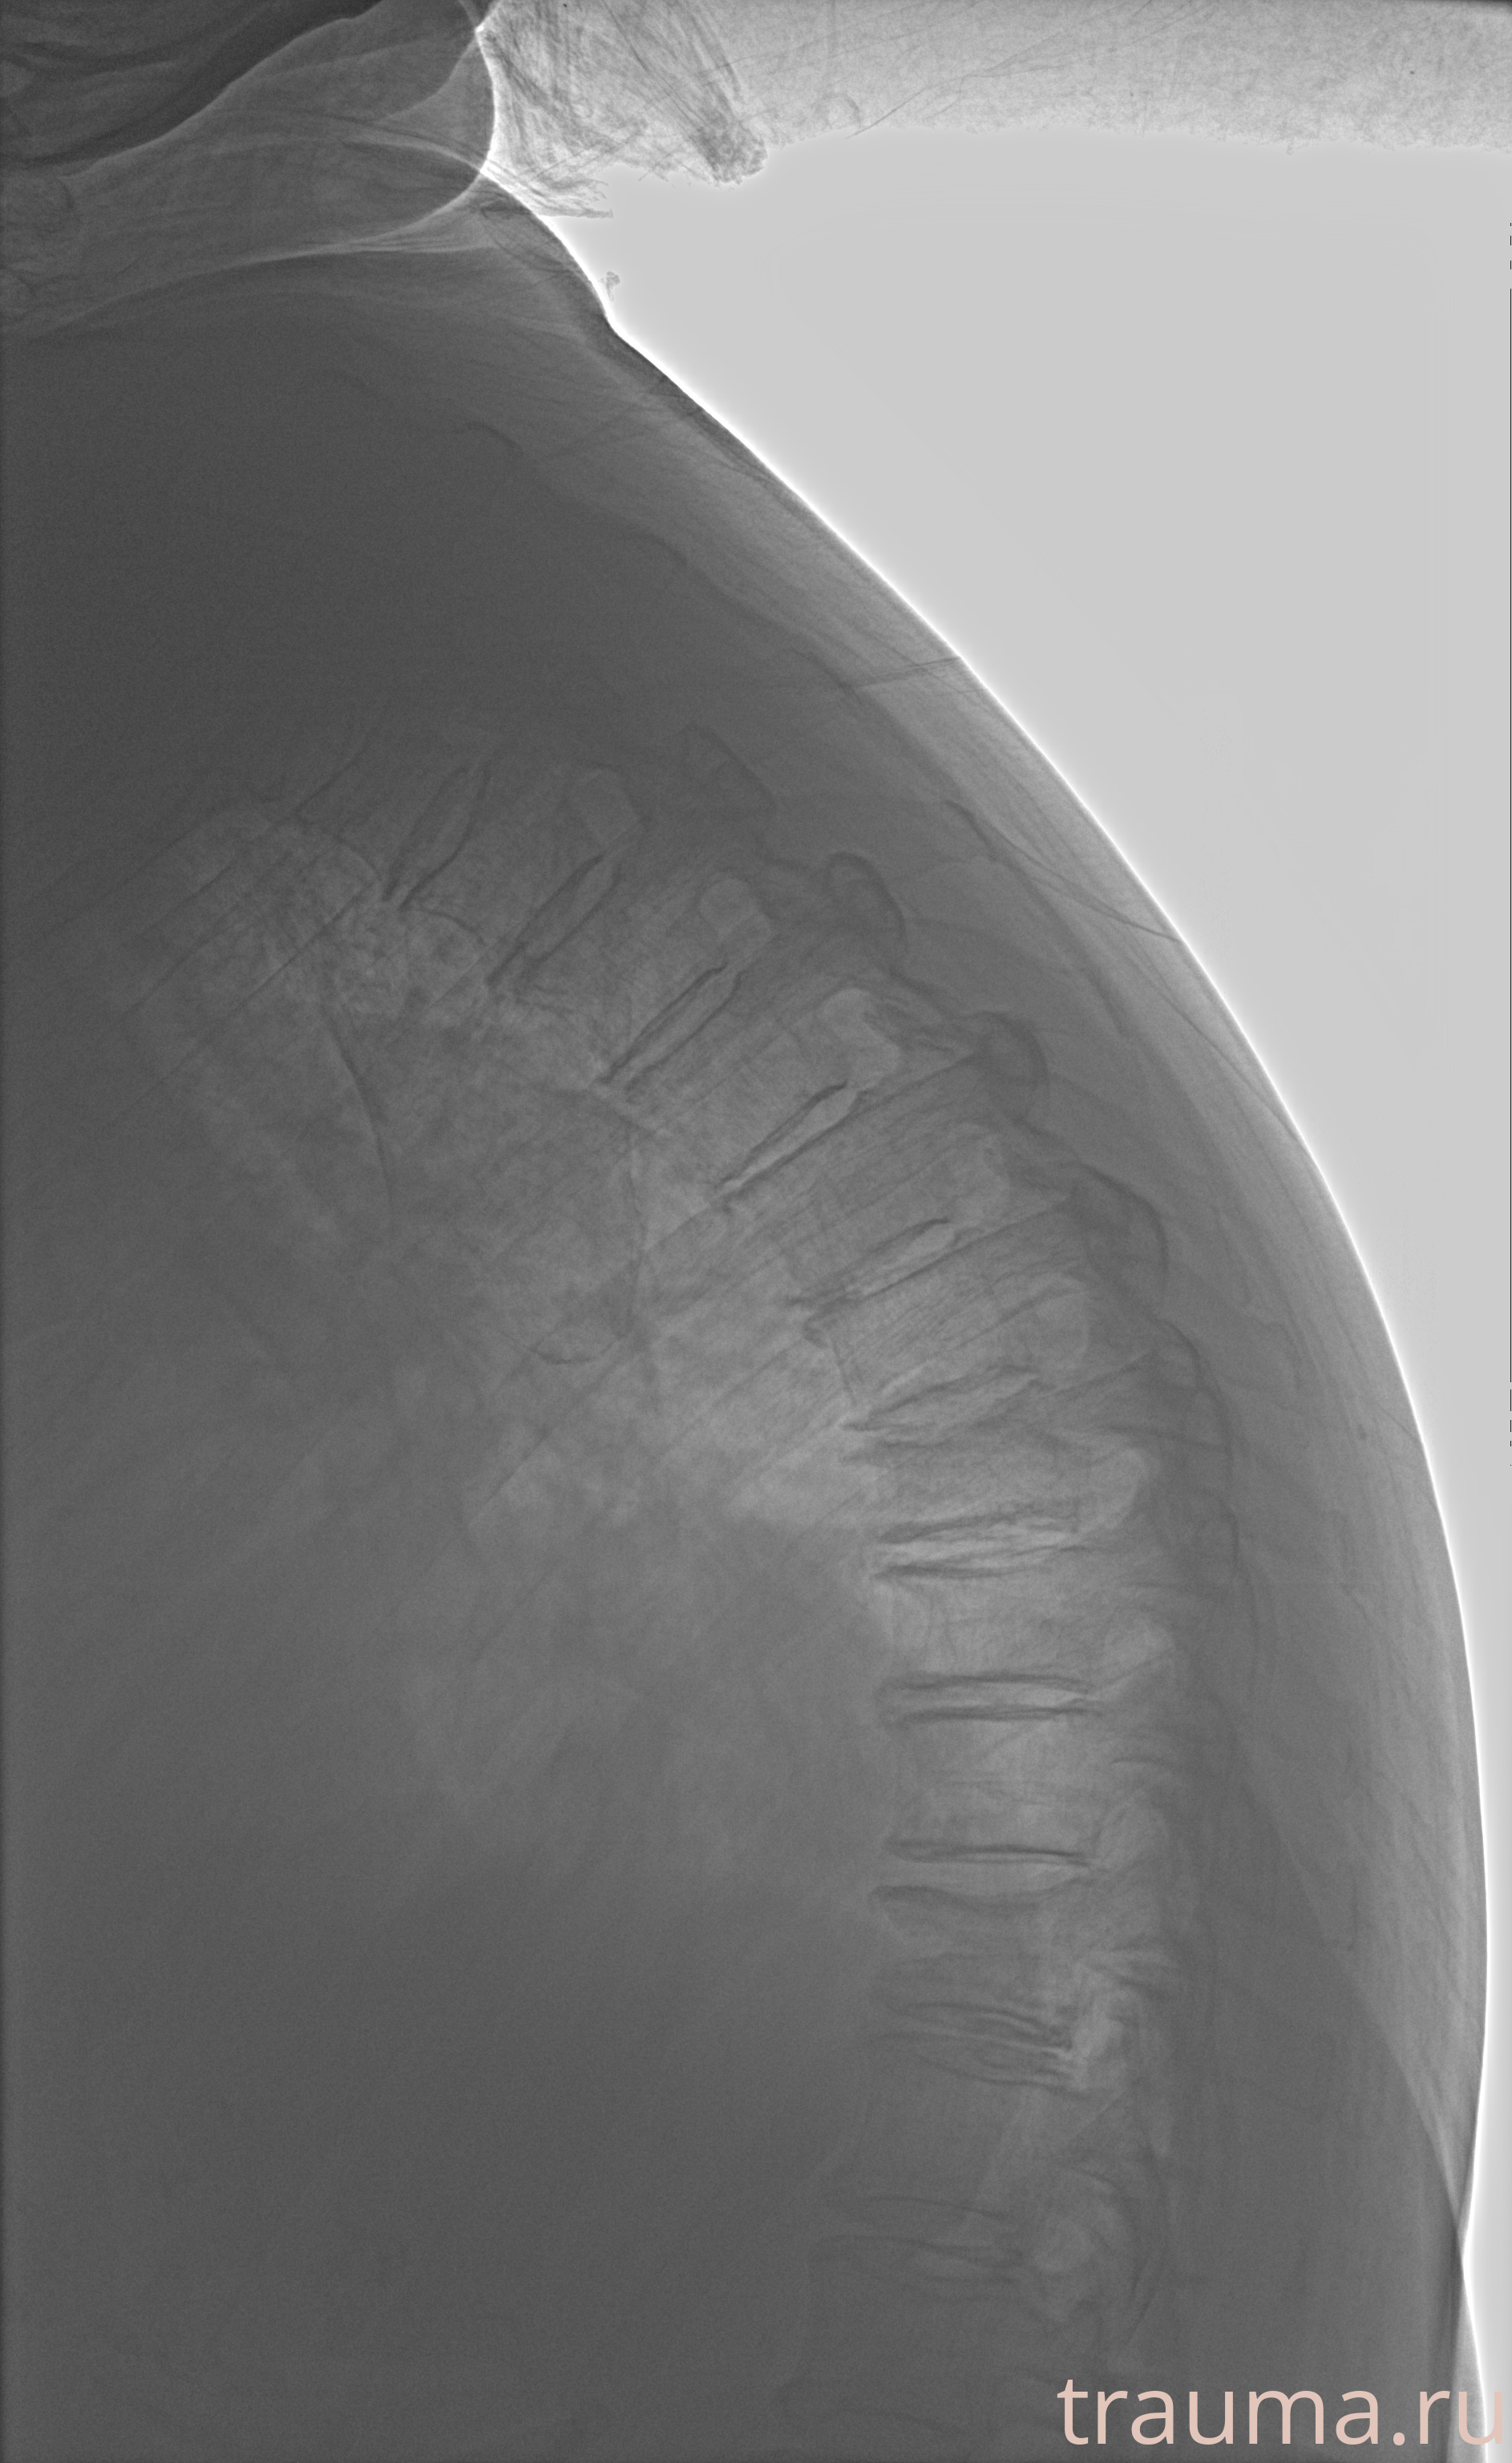

Рентгенограммы

Рентген на дому: по вашему адресу приезжает врач-рентгенолог, травматолог-ортопед с мобильным рентгеновским аппаратом, проводит диагностику травмы или заболевания, делает необходимые рентгенограммы, дает рекомендации по дальнейшему лечению. Получить качественные снимки в домашних условиях возможно благодаря уникальной методике, разработанной МосРентген Центром для института  Склифосовского